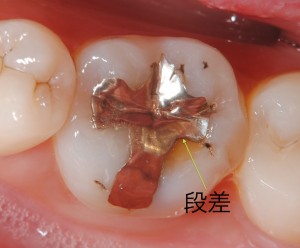

先日、従業員の口腔内診査を行った所、15年くらい前にセットした金属(インレー)と歯の境目に段差が生じていました。レントゲン診査では2次齲蝕の可能性がありましたが外してみて意外と虫歯が進行していて本人もびっくりしていました、虫歯を除去した後はコンポジットレジンで修復を行いました。